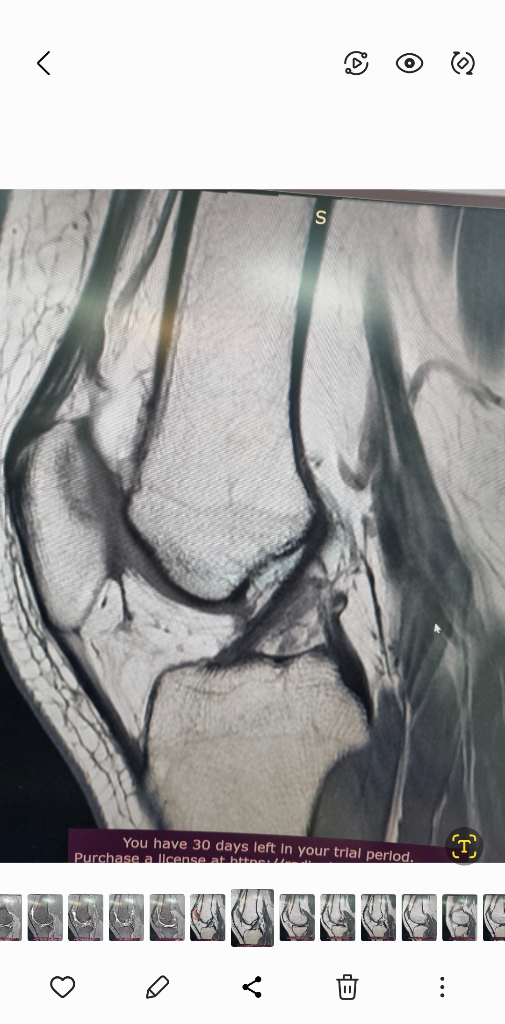

1. 추벽이 아닙니다.

2. 슬개골 관절면에 외상으로 인한 골수부종입니다.

3. 관절면 손상여부는 첨부해주신 영상만으로 알 수 없습니다